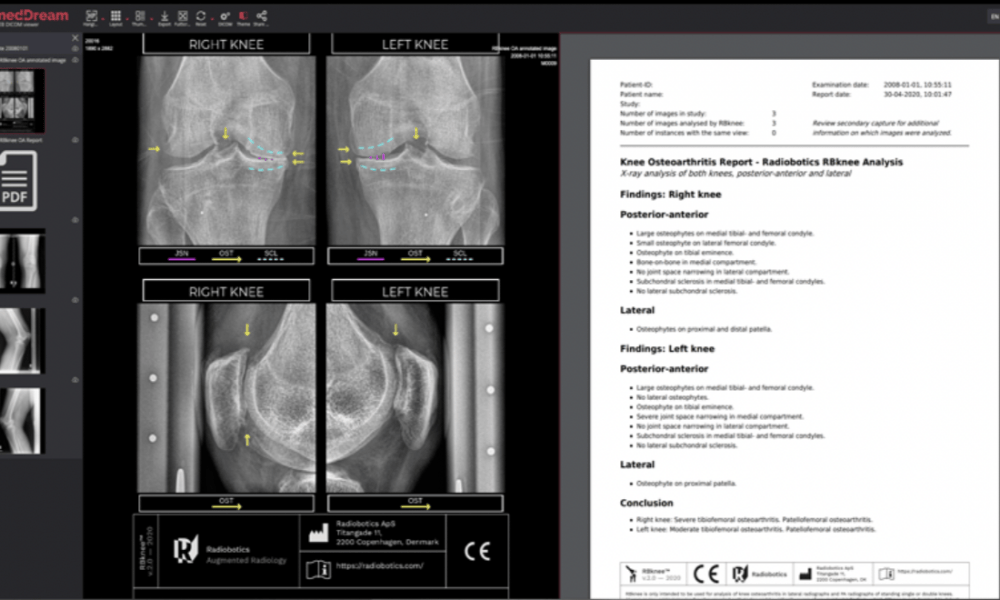

Using artificial intelligence, machine learning and computer vision, Radiobotics’ medical devices can ‘look’ at the images, detect major findings, analyse them and produce a text report and conclusion along with a visual overlay to support the radiologist’s decision.

Radiobotics has developed several products since launching in 2017; including the CE marked RBKnee and RBHip. The latter aims to identify when a patient is starting to deteriorate so they can be offered preventative treatment. The device scans for hip dysplasia, a condition that precedes osteoarthritis and often goes undiagnosed.